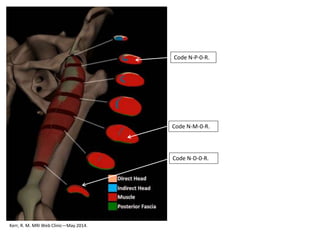

Examples Indirect RF Injuries

with Negative MRI

Kerr, R. M. MRI Web Clinic—May 2014.

Code N-D-0-R.

Code N-P-0-R.

Code N-M-0-R.